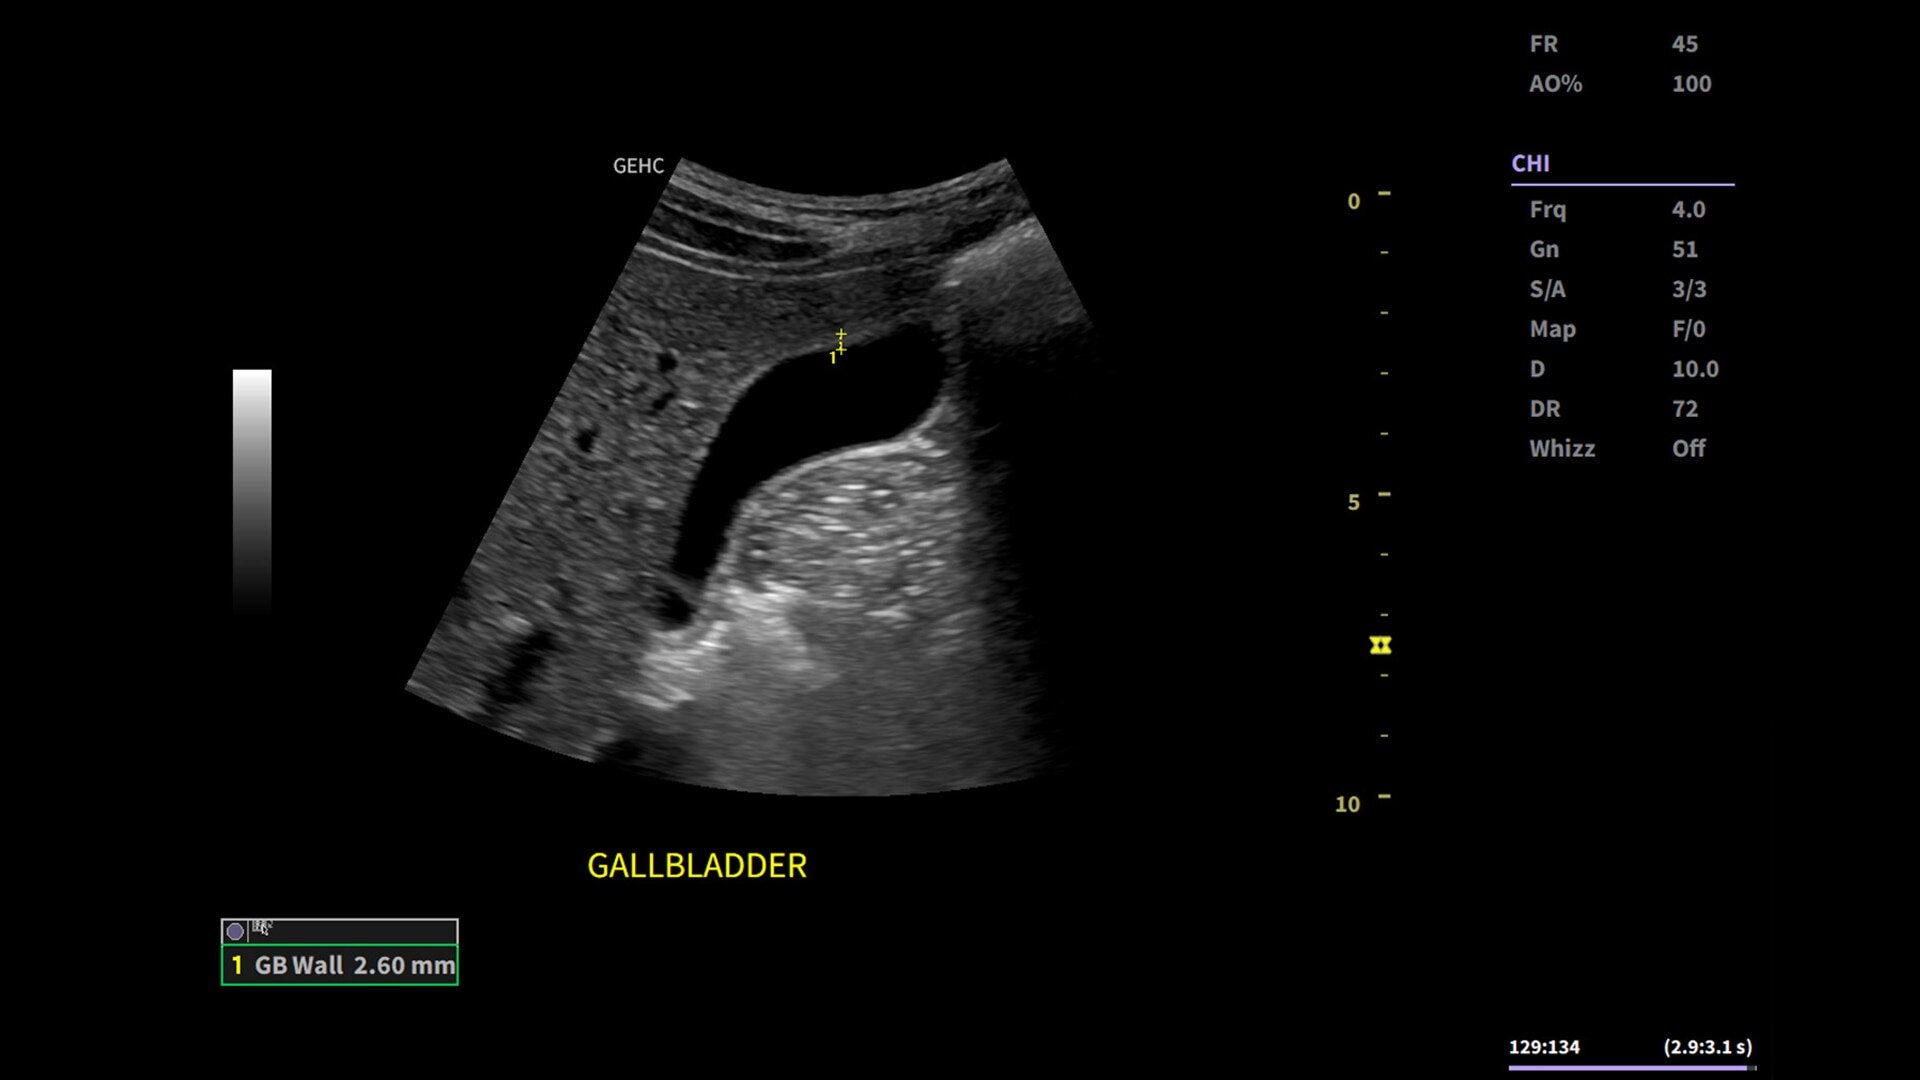

Whizz Label

AI-enabled labeling of the right kidney, gallbladder and liver

• Use automated labeling in the RUQ with Whizz Label